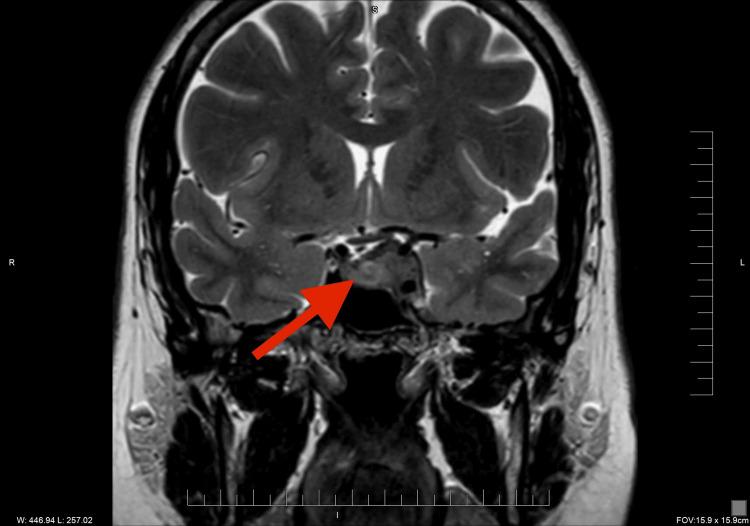

Sex hormones play a crucial role in the development and growth of meningioma. It was observed that meningiomas increase in size and become more symptomatic during pregnancy. Similarly, the use of hormonal therapy, including gonadotropin-releasing hormone (GnRH) agonist, can be associated with an increased risk for meningioma. We reported a 45-year-old woman with a past medical history of hypothyroidism and mild hyperprolactinemia who received hormonal therapy for infertility, including GnRH. She has experienced a persistent headache and left retro-orbital pain with eye movement. Her MRI brain scan revealed a soft tissue mass involving the sellar and left cavernous sinus with a slight impingement of the optic chiasm and left optic nerve, concerning for meningioma or pituitary adenoma. Further laboratory workup showed secondary adrenal insufficiency, which was treated with replacement glucocorticoid therapy. Following tumor resection and histological examination, the diagnosis of sellar meningioma was confirmed. This case report shows a rare association of fertility hormonal treatment with sellar meningioma and how it is challenging to distinguish meningioma from other sellar masses, such as pituitary adenoma, based on clinical presentation and imaging studies.

性激素在脑膜瘤的发生和发展中起着至关重要的作用。据观察,脑膜瘤在孕期体积会增大且症状会加重。同样,使用包括促性腺激素释放激素(GnRH)激动剂在内的激素疗法,可能会增加患脑膜瘤的风险。我们报告了一名45岁女性,她有甲状腺功能减退和轻度高泌乳素血症病史,因不孕症接受了包括GnRH在内的激素治疗。她一直头痛,眼球活动时伴有左眶后疼痛。她的脑部MRI扫描显示鞍区和左侧海绵窦有一软组织肿块,对视交叉和左侧视神经有轻微压迫,怀疑为脑膜瘤或垂体腺瘤。进一步的实验室检查显示继发性肾上腺功能不全,并接受了糖皮质激素替代治疗。肿瘤切除及组织学检查后,确诊为鞍区脑膜瘤。本病例报告显示了生育激素治疗与鞍区脑膜瘤之间罕见的关联,以及基于临床表现和影像学研究将脑膜瘤与其他鞍区肿块(如垂体腺瘤)区分开来具有挑战性。